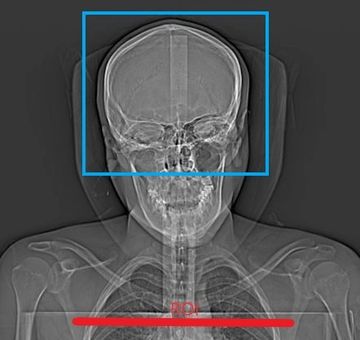

125 ml omnipaque 350 injected at 4cc/second.

Bolus track on the Aortic Arch at 80 HU.

Do Routine Head W/O 3.75 x 3.75 GE / 3.0 x 3.0 Siemens bone and standard algorithms C-2 through vertex of head

Helical: 2.5 x 2.0 GE standard / 2.0 x 2.0 Siemens standard 800 W 100 L

Recons:0.625 x 0.625 GE standard 400 W 40 L / 0.75 x 0.7 Siemens standard 400 W 40 L

1 x 1 mm 800 W 100 L

coronal MIP 14 x 4 GE / 16 x 4 Siemens 800 W 100 L

sagittal MIP 14 x 4 GE / 16 x 4 Siemens 800 W 100 L

axial MIP 14 x 4 GE / 16 x 4 Siemens 800 W 100 L

C.O.W. MIP 14 x 4 GE / 16 x 4 Siemens 800 W 100 L

coronal MPR 2 x 2

sagittal MPR 2 x 2

VRT of COW rotate and tumble every 10 degrees